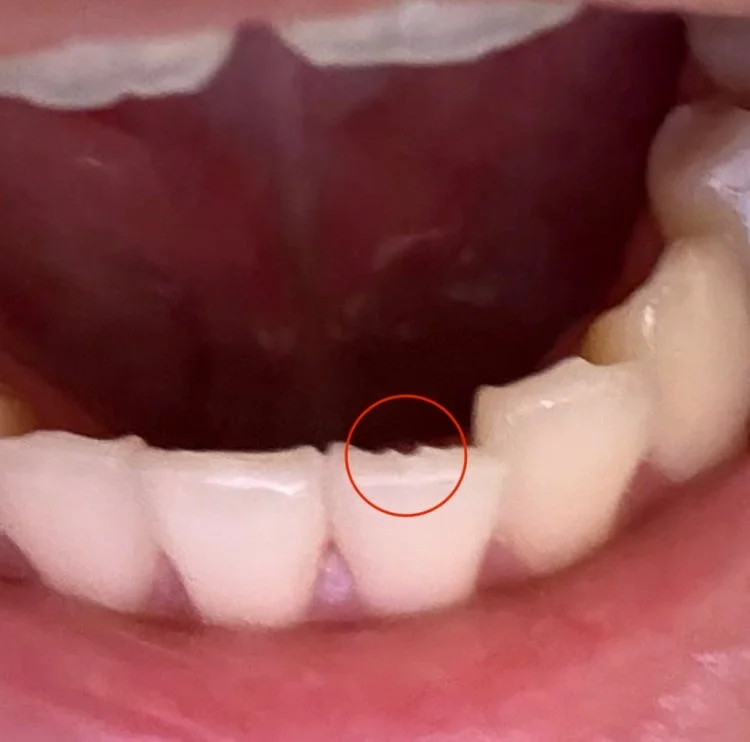

2025-10-04 03:39:11아랫니 앞니쪽이 살짝 깨졌어요

육포를 뜯어먹다가 딱. 하는 소리가 느껴져서 봤더니 아랫니가 살짝 깨졌어요 만져보면 날카로워져서 그러는데 치과가도 의미가 있나요??

Dr.s Diagnosis안녕하세요. 아랫니 앞니 쪽이 깨진 것에 대해 걱정이 많으시겠네요. 사진으로 보니 깨진 부분이 작아 보이지만, 날카로워졌다고 느끼시는 만큼 불편함이 있을 수 있습니다.